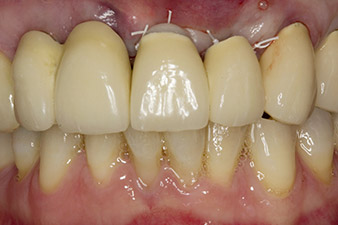

When the patient first presented, teeth 21, 22 and 23 had been restored with splinted crowns, now 19 years old, which were bonded to the implants at positions 12/11 by an attachment (cf. Fig. 2).

Tooth 23 displayed a horizontal-coronal fracture and was restored with a post and core build-up for the temporary restoration. The plan was to place a zirconium oxide bridge on the existing implants at positions 12 and 11 and to place two new implants at positions 22 and 23.

Following primary healing, the soft tissues were shaped using the basally lined bridge. Two months later the site was exposed by a slightly palatal alveolar ridge incision (Fig 2). The dimensions of the alveolar bone proved to be sufficient at position 22. Figures 2 and 4 show the preparation of the implant bed, the tapping and the implantation using Implantmed.